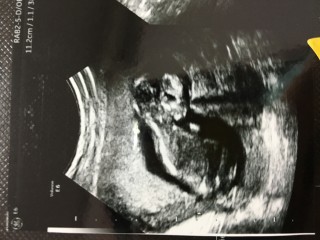

約6センチ。順調に成長していました。背骨がだいぶしっかりしてきました。顎も作られているそうです。「お腹のはしっこが好きな子だね~!」って言われました。

12週目での4Dエコー! この日からお腹のエコーに切り替わりました。 こんなにはっきり赤ちゃんが見えるなんて、本当に感激です。「頭かいてるね~!とても元気ですよ」と先生。想像以上に手足が動いていました! 寝ているときはあまり動かないそうで、起きてる時をみれてよかったです(*´-`)

半年前に流産をして、この12週の検診まで毎日ハラハラでした。「手が顔の横にあってこれ可愛いんじゃない」と言って40枚くらいの写真の中から先生が選んでくれました。次は16週です!